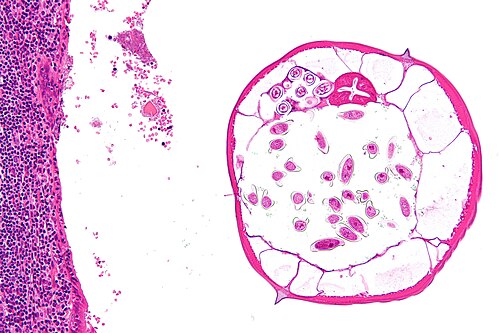

Provided clinical history

17 year old woman, appendicitis

Site

Appendix

Low magnification. H&E stain.

Appendix looked normal at time of surgery.

The abnormality is in the lumen.